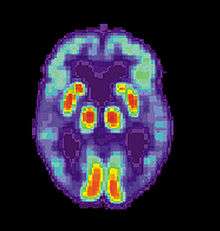

Alzheimer's disease (AD) is a progressive, degenerative and fatal brain disease, in which cell to cell connections in the brain are lost. Alzheimer's disease is the most common form of dementia.[2] Globally approximately 1–5% of the population is affected by Alzheimer's disease.[3] Women are disproportionately the victims of Alzheimer's disease, with evidence suggesting that women with AD display more severe cognitive impairment relative to age-matched males with AD, as well as a more rapid rate of cognitive decline.[4]

PET scan of brain with AD - Image courtesy of US National Institute on Aging Alzheimer's Disease Education and Referral Center